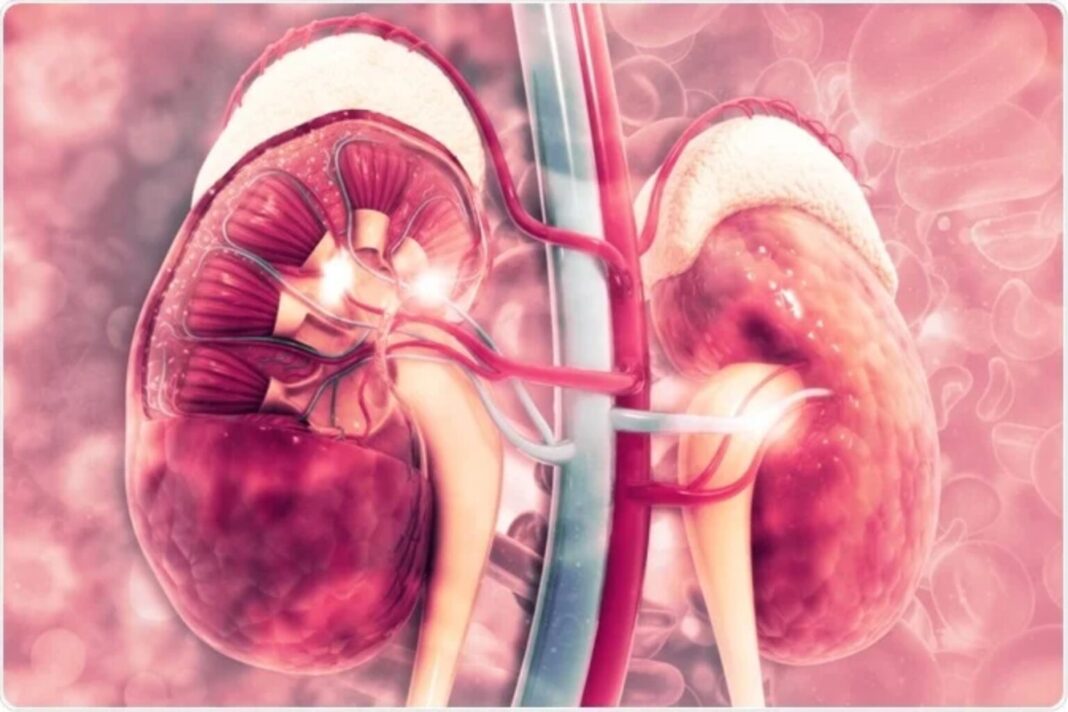

Εάν ο γιατρός σας σας έχει πει ότι έχετε χρόνια νεφρική νόσο (ΧΝΝ), μπορεί να σας προκαλέσει σοκ. Αν και έχουν γίνει πολλές ιατρικές πρόοδοι στη θεραπεία της νόσου των νεφρών και του ουροποιητικού συστήματος, οι συναισθηματικές επιπτώσεις της νεφρικής ανεπάρκειας στους ασθενείς και τις οικογένειές τους παραμένουν μεγάλες, επειδή περιλαμβάνει αλλαγές σε διάφορα επίπεδα. Το να ζείτε με χρόνια νεφρική νόσο μπορεί συχνά να είναι προκλητικό και οδυνηρό, ειδικά εάν η ασθένεια εξελίσσεται και αντιμετωπίζετε την πιθανότητα αιμοκάθαρσης.

;Η νεφρική νόσος που προκαλείται από τον σακχαρώδη διαβήτη και την υπέρταση παίρνει πλέον διαστάσεις επιδημίας. Η παχυσαρκία και η νεφρική νόσος που σχετίζεται με τον τρόπο ζωής είναι επίσης σε άνοδο. «Λοιμώξεις των νεφρών και του ουροποιητικού συστήματος, πέτρες στα νεφρά, ουσία και φάρμακα α